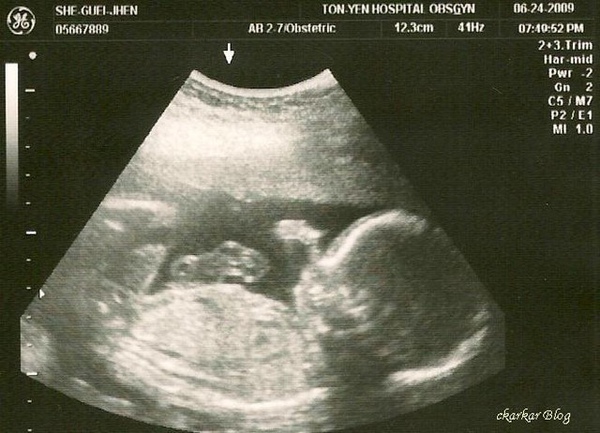

媽媽體重增加2kg,胃口有慢慢變好了,也常常感覺胎動,6/24產檢一樣是全家出動